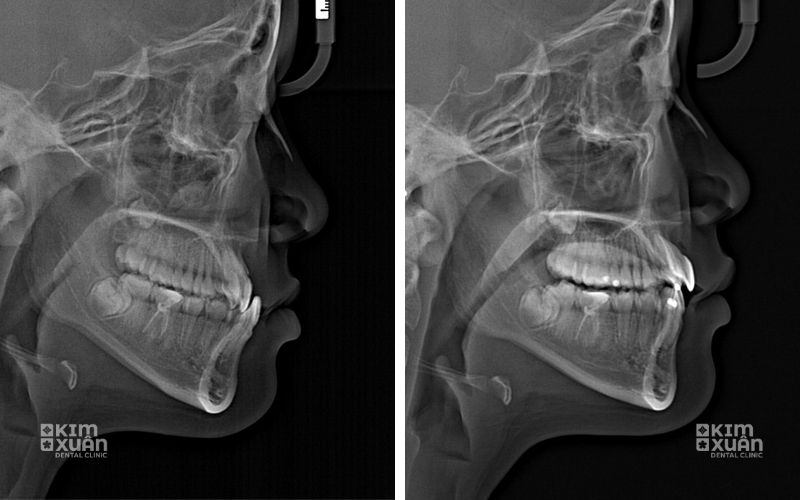

4.1. Mức độ móm của răng và xương hàm

Móm nhẹ, chủ yếu do răng: Kế hoạch điều trị đơn giản hơn nên chi phí thấp hơn

Móm nặng, kèm lệch xương hàm: Điều trị phức tạp, thời gian kéo dài, có thể cần phối hợp nhiều kỹ thuật nên chi phí cao hơn

Thời gian niềng răng móm thường kéo dài 18 - 30 tháng, tùy thuộc vào tình trạng răng, mức độ khớp cắn ngược và sự hợp tác của người niềng. Thời gian càng dài, chi phí điều trị có thể càng cao.

Trang thiết bị chẩn đoán hiện đại như CT Cone Beam, scan răng 3D